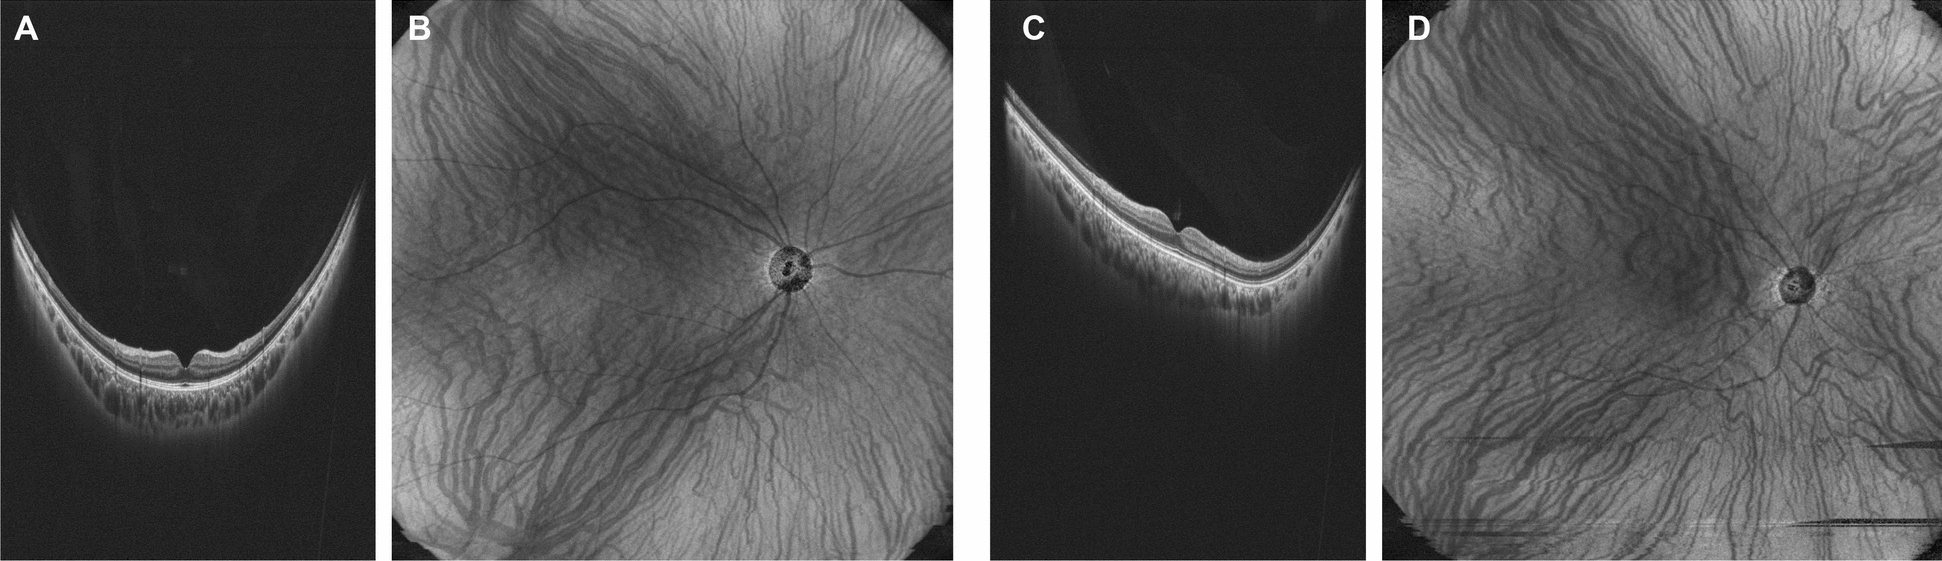

Methods: This single-center retrospective study included healthy subjects. UWF-OCT images of normal subjects were stretched vertically to enhance the macula's shape and classified into IPS (n = 16) and non-IPS (n = 113) groups with or without propensity score matching (PSM) for age, sex, and ocular axis length. The HVRPs were subjectively classified into symmetry, superior dominant, and inferior dominant. Differences in the proportions of the patterns between the two groups were compared using Fisher's exact test.

Results: In the non-IPS group, 65 (57.5%) individuals had a symmetric pattern of Haller's vessels, 32 (28.3%) had an upper-dominant pattern, and 16 (14.1%) had a lower-dominant pattern. In the IPS group, 14 eyes (87.5%) presented an upper dominant pattern, and 2 (12.5%) presented a symmetric pattern. There was a significant difference in vascular running patterns between the two groups (P < 0.001). After the PSM, a similar trend was confirmed.